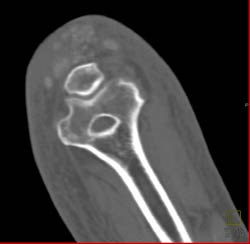

Gout